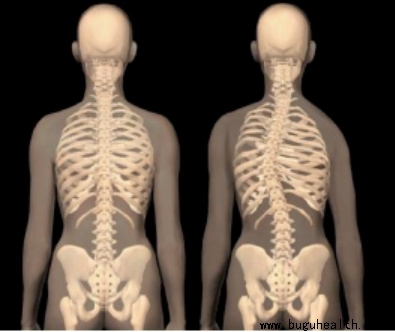

脊柱侧弯是脊柱的非正常弯曲。正常的脊柱在肩部有向后的弯曲,而在腰部有向前的弯曲。典型的脊柱侧弯包括三维的脊柱和肋骨畸形。根据度数的变化,脊柱从侧面弯曲,有时椎骨有轻微旋转,导致髋部或肩部出现不平衡。.....

脊椎侧弯是一种常见的骨骼问题,在站姿下,不管从正面或背面看,正常的脊椎排列应该是身体左右两边对称,并且正常的脊椎排列从上到下是呈一直线的。.....